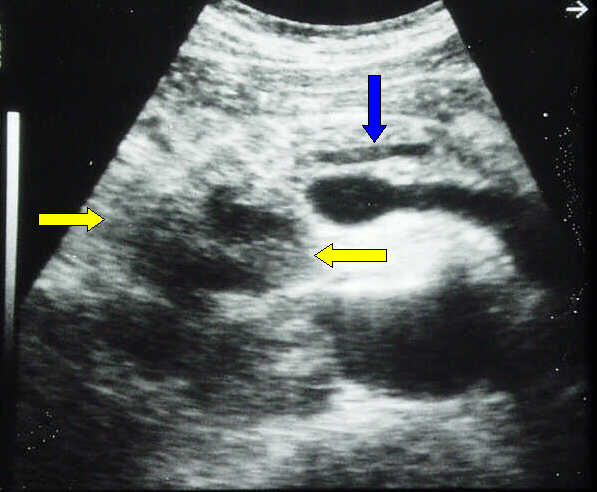

Transverse scan. Large, echo-poor, inhomogeneous pancreatic head cancer (yellow arrows), with irregular, lobulated margins and necrotic areas. The main pancreatic duct is slightly dilated (blue arrow).